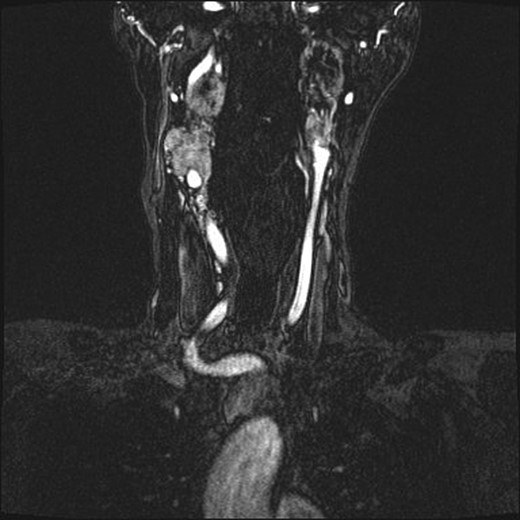

(A and B) Magnetic resonance images, coronal planes, highlight three of the four previously noted cervical PGLs decreasing in size, with the right inferior PGL remaining unchanged.

Radiation therapy was selected in the setting of local extension of the tumors and proximity to critical neurovascular structures. The patient underwent stereotactic radiation treatment of 30 Gy over 5 days, with a positive response on imaging (Fig. 2) and a reduced frequency of syncopal events.